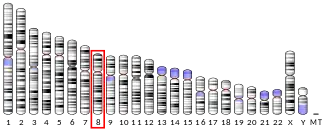

The FGFR1 gene is located on human chromosome 8 at position p11.23 (i.e. 8p11.23), has 24 exons, and codes for a Precursor mRNA that is alternatively spliced at exons 8A or 8B thereby generating two mRNAs coding for two FGFR1 isoforms, FGFR1-IIIb (also termed FGFR1b) and FGFR1-IIIc (also termed FGFR1c), respectively. Although these two isoforms have different tissue distributions and FGF-binding affinities, FGFR1-IIIc appears responsible for most of functions of the FGFR1 gene while FGFR1-IIIb appears to have only a minor, somewhat redundant functional role.[7][8] There are four other members of the FGFR1 gene family: FGFR2, FGFR3, FGFR4, and Fibroblast growth factor receptor-like 1 (FGFRL1). The FGFR1 gene, similar to the FGFR2-4 genes are commonly activated in human cancers as a result of their duplication, fusion with other genes, and point mutation; they are therefore classified as proto-oncogenes.[9]